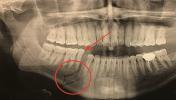

Целью проведения данной комиссионной судебно-медицинской экспертизы являлась всесторонняя оценка необходимости медицинских услуг, оказанных гражданину после полученных им телесных повреждений. Основная задача экспертов заключалась в установлении причинно-следственной связи между травмой челюсти, возникшей в результате конфликта [дата конфликта], и последующим обращением за специализированной медицинской помощью, включая стоматологические процедуры, в коммерческой клинике "Медицинский центр Интердентос". Экспертам предстояло определить, были ли оказанные услуги по протезированию зуба и реконструкции костной ткани объективно необходимы с медицинской точки зрения, учитывая характер полученных повреждений и стандарты оказания медицинской помощи. В процессе исследования эксперты сталкивались с необходимостью анализа медицинской терминологии, сопоставления различных медицинских заключений и выработанных планов лечения, а также с оценкой соответствия назначенных процедур общепринятым клиническим рекомендациям и действующим нормативным актам, регулирующим предоставление медицинских услуг.

Иллюстрации